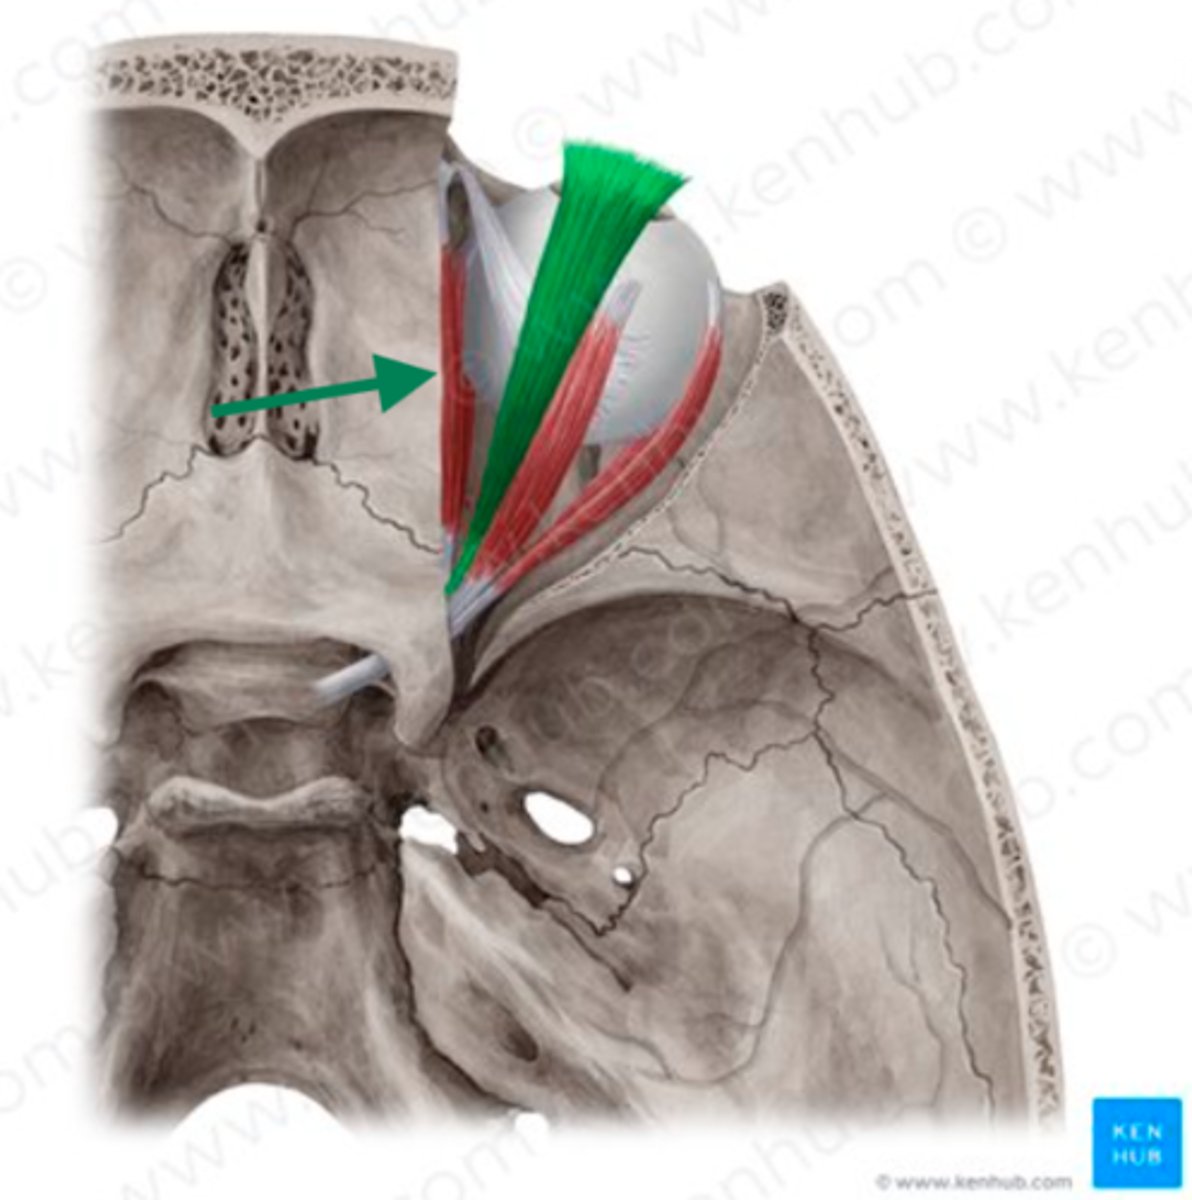

cribriform plate

sphenoidal sinus

anterior cranial fossa

frontal bone

ethmoid bone (perpendicular plate)